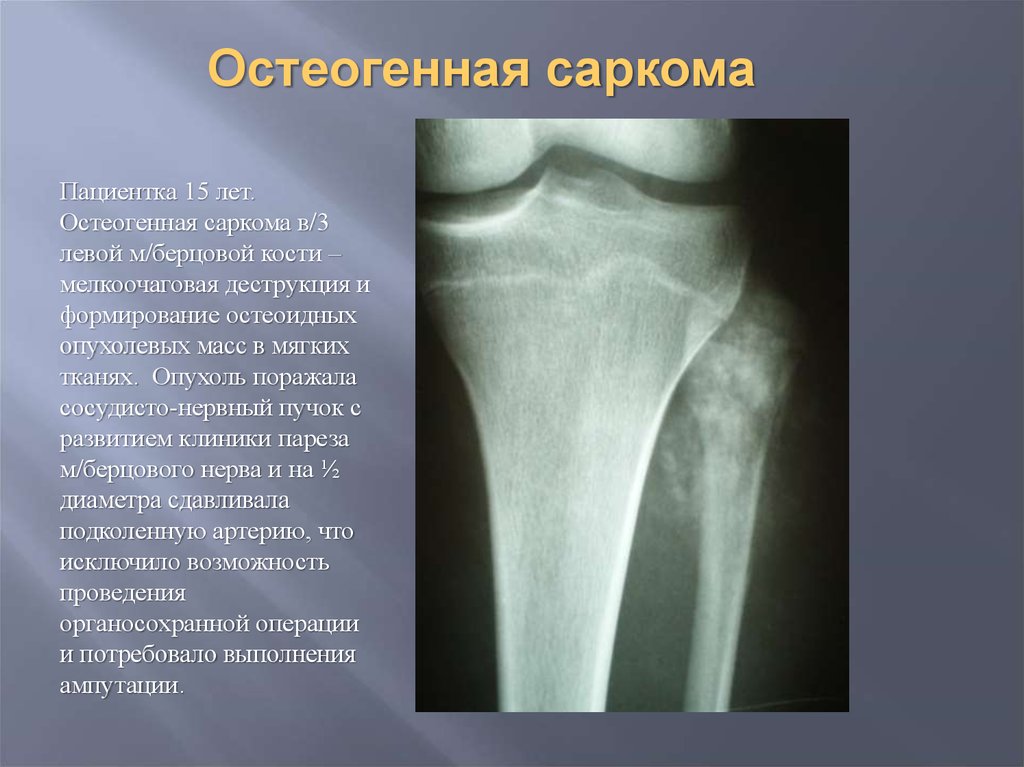

Рентгеновские снимки саркомы плечевого сустава